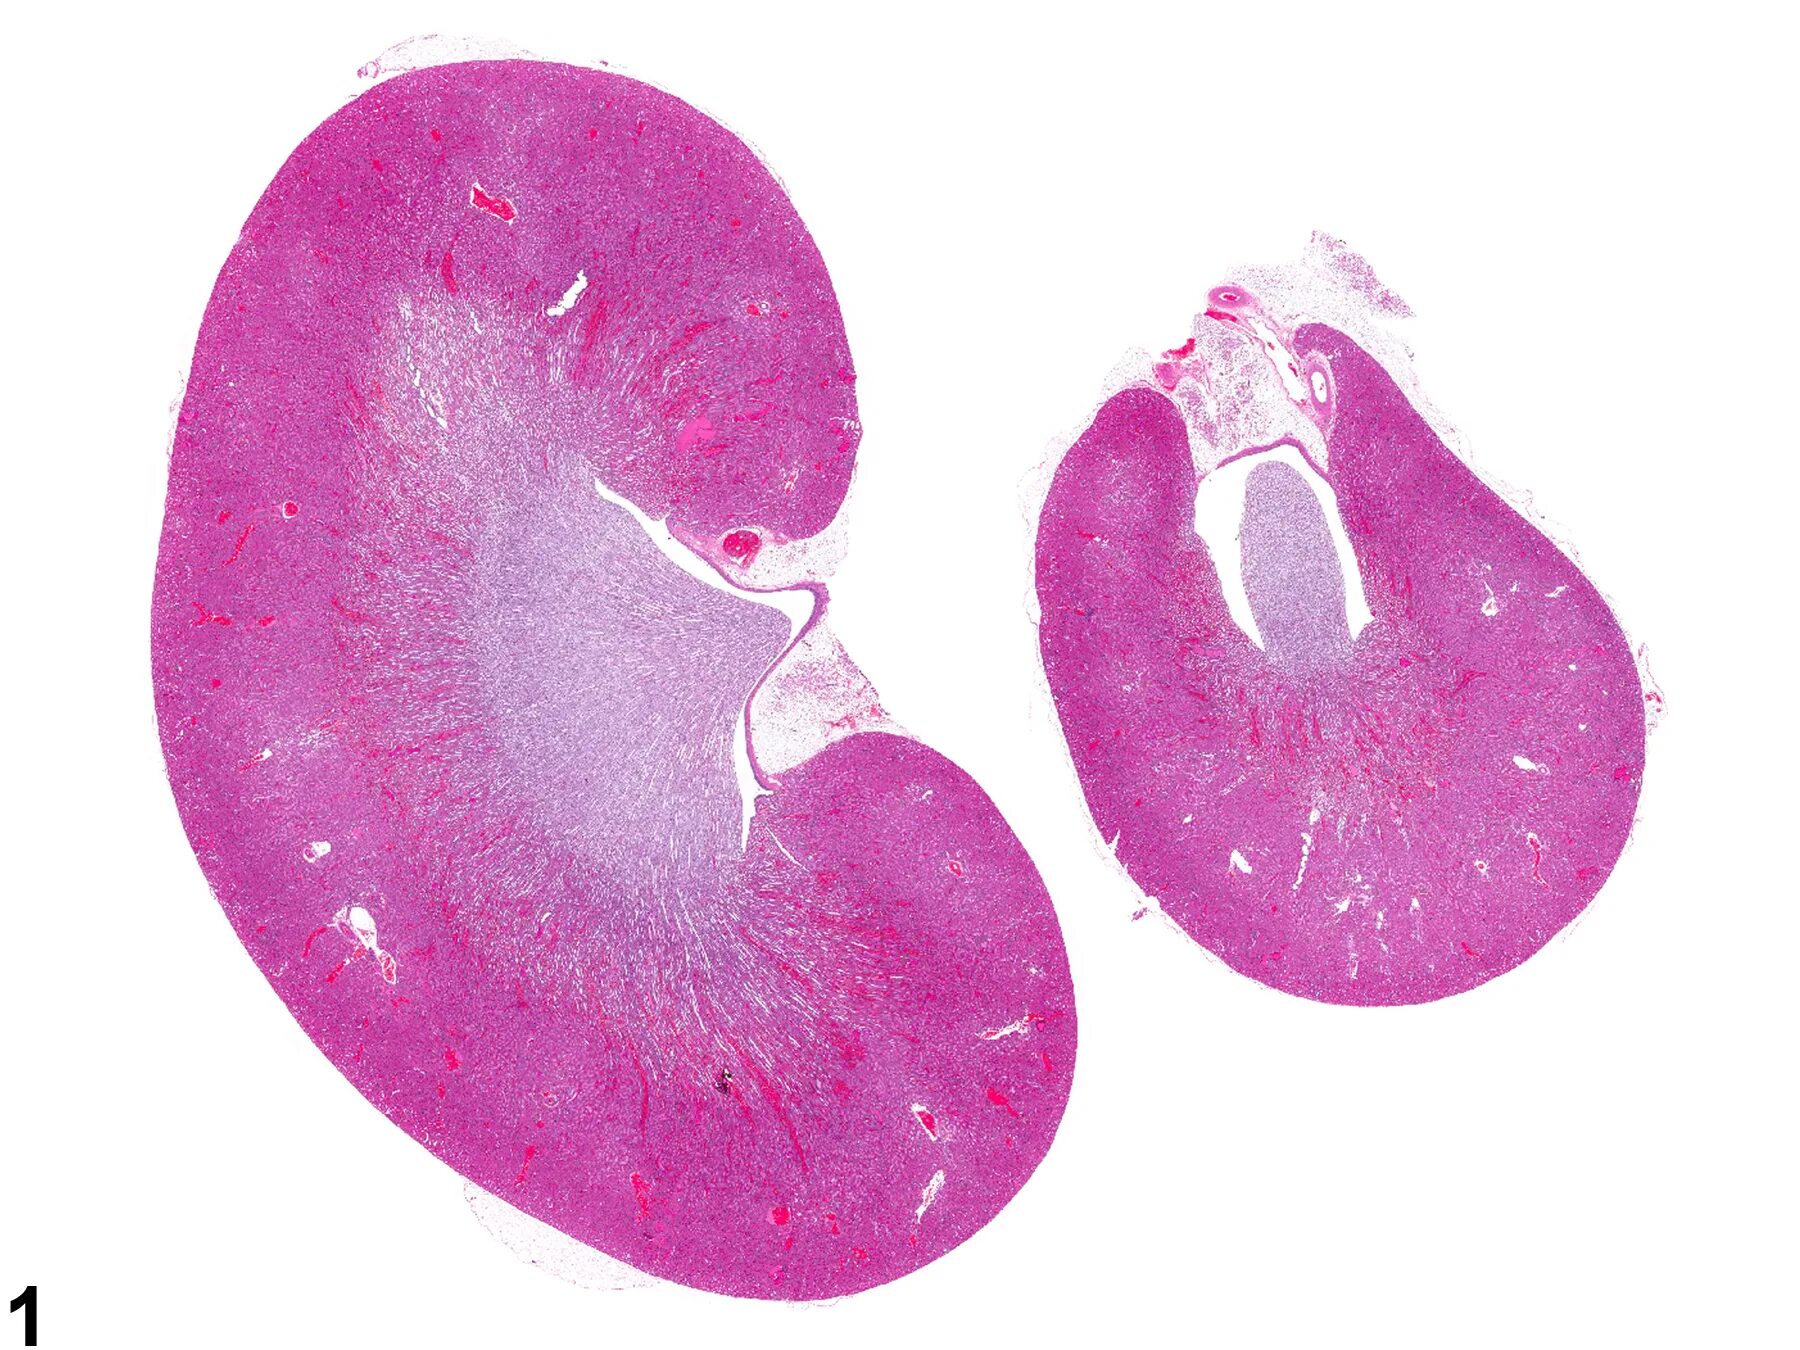

Гистология почки